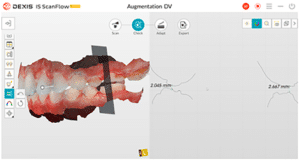

Lors de cette première consultation, en plus de l’examen clinique, on réalise une empreinte optique (Fig.2).

Fig.2.

Elle a deux buts. Le premier relève de la communication : il est plus facile pour la patiente de se rendre compte de l’état d’usure de ses dents avec une image 3D en plus des photographies et du miroir de courtoisie. Le deuxième but est l’analyse de l’occlusion. Grâce au logiciel d’exploitation (ici, Dexis IS Scan Flow), on se rend bien compte que l’occlusion est serrée avec des contacts extrêmement forts à droite (en rouge sur le Scan Flow). Il est alors facile de conclure et d’expliquer dès à présent à la patiente qu’il est impossible de restaurer son sourire dans cette situation occlusale. Pour redonner de la hauteur aux dents antérieures il faut de la place, créée soit par soustraction en préparant les dents antérieures, soit par addition en relevant la hauteur des dents postérieures. La patiente fait rapidement son choix. Pour nous, cela signifie qu’il va falloir augmenter la DVO.